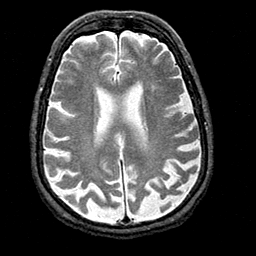

Alzheimer's disease MR T2-weighted -- Slice #30

[Home][Help][Clinical][Tour 1][Tour 2] Slice 30